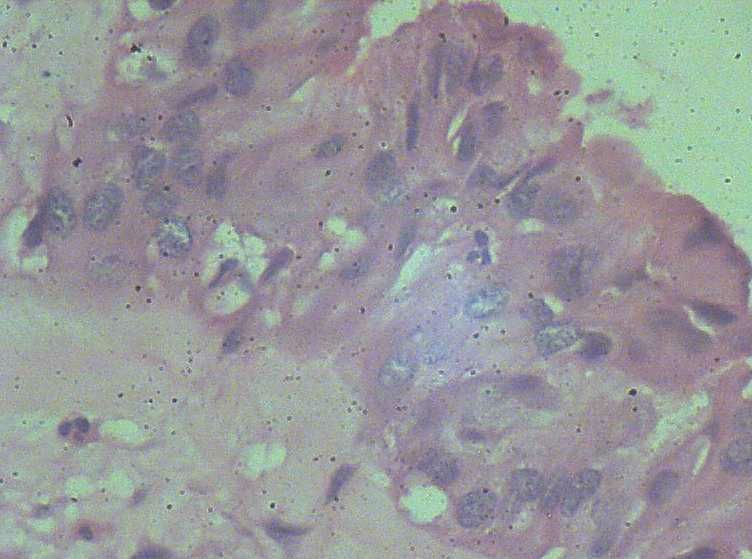

女,27岁,剖宫产术中见一侧卵巢一肿物。大体:椭圆形肿物大小3*2*1.5表面光滑,剖开内容为浅黄色胶状物,质均,囊内壁较光滑,部分见细小乳结构。

可见增生的上皮,形成乳头或微乳头,见到钉突和出芽式的生长,漂浮的上皮细胞簇,细胞核轻-中度不典型增生。

从所给的图片来看,发交界性浆液性乳头状囊腺瘤,仔细找找是否有微浸润的存在,再排除浸润成为癌的可能性。

浆液性乳头状瘤是可以确定的。

是否是交界性?图片中乳头分支复杂,细胞确实有异型性。但是不知道在妊娠期,激素水平和平时不同,这时的标准怎么掌握?请高手指教。